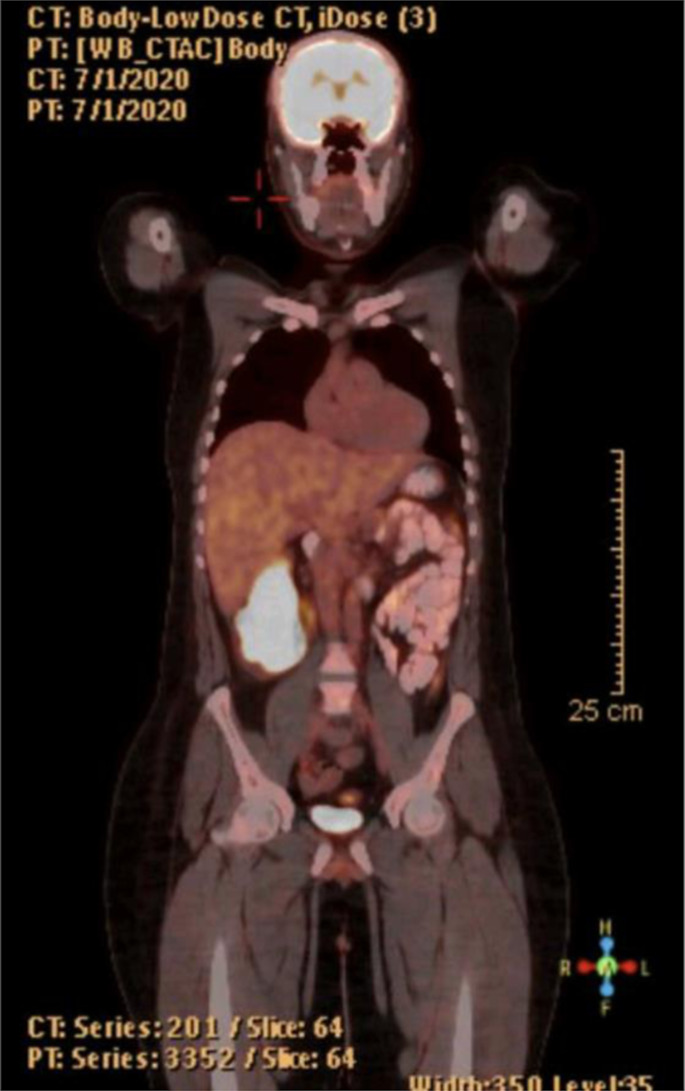

Case presentation: We present a 39-year-old male with a 9-year history of UC who experienced severe anemia and hematochezia. Imaging and histopathological analysis confirmed a diagnosis of stage IIIB ASC of the right colon. The patient underwent total colectomy followed by adjuvant chemotherapy (XELOX), ileoanal pouch reconstruction, and stoma closure. After 56 months of follow-up, he remains disease-free with good pouch function.